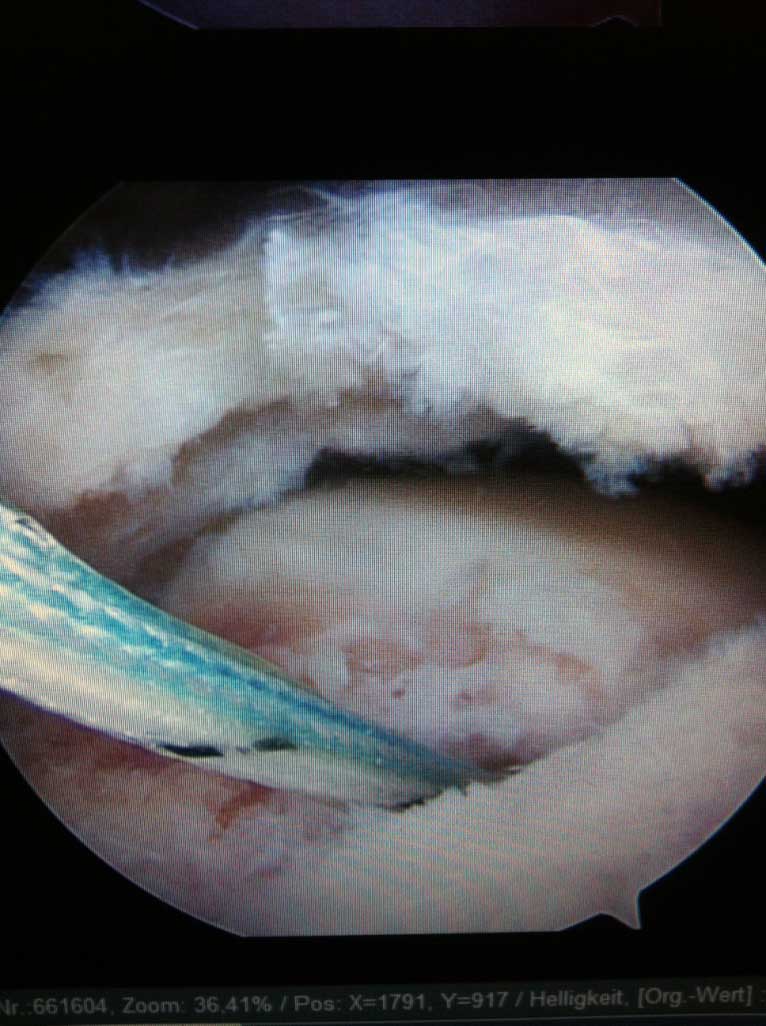

Wird die Indikation zur Sehnennaht / Rekonstruktion der gerissenen Sehnen gestellt, so wird die Operation in unseren Händen ausschließlich arthroskopisch (Schlüsselloch Operation) durch 3 - 6 kleinen Stichinzisionen (3-4mm) durchgeführt. Dieses operative Verfahren ist maximal zu den schulterumgebenden  Weichteilen schonend.

Zum Sehnenriss im Bereich der Schulter kann sowohl Unfall als auch Verschleißbedingt kommen. Kleine Risse verursachen eher Schmerzen im B. der Schulter und des Oberarmes, die grossen sind neben Schmerzen auch mit wesentlicher Kraftminderung und Beeinträchtigung der aktiven Armbeweglichkeit in der Schulter vergesellschaftet.

Die aktiven Stabilisatoren sind die gelenkübergreifenden Sehnen, welche in Form d.s.g. Rotatorenmanschette, seitlich am Oberarmkopf ansetzen. Deren Aufgabe ist sowohl den OA Kopf in der flachen Pfanne zu zentrieren als auch mit dem Arm in der Schulter zu bewegen.